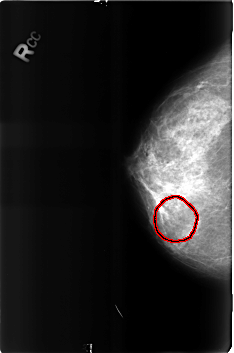

B_3160_1.RIGHT_CC

FILE: B_3160_1.RIGHT_CC.OVERLAY

TOTAL_ABNORMALITIES 1

ABNORMALITY 1

LESION_TYPE MASS SHAPE ROUND MARGINS N/A

ASSESSMENT 2

SUBTLETY 3

PATHOLOGY BENIGN

TOTAL_OUTLINES 1

BOUNDARY

RIGHT_CC LINES 4584 PIXELS_PER_LINE 3040 BITS_PER_PIXEL 12 RESOLUTION 50 OVERLAY